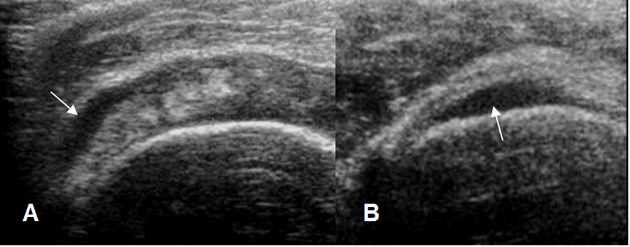

Fig 128. Tendinitis del supraespinoso.

A y B: Ecografía coronal. Cambios inflamatorios del supraespinoso, con líquido en la superficie bursal en A y sobre la superficie humeral en B.